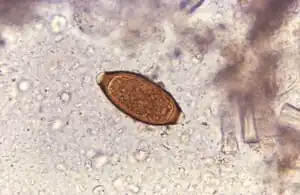

Ouăle au o forma destul de caracteristică: de culoare galben-portocaliu, acestea sunt ovoide, măsoară 50-65 × 23-30 μm, posedă o coajă groasă brună și un dop mucos la cei 2 poli, oferindu-le un aspect de "lămâie". Ele nu sunt embrionate (nu sunt infectante) în materiile fecale proaspăt emise . Dopul mucos de la poli reprezintă niște proeminențe albe, compuse din microfibrile mucoide.

Diagnosticul infecției cu tricocefali este ușor confirmat prin punerea în evidență a ouălor la examenul coproparazitologic al scaunului. Ouăle au o forma destul de caracteristică: sunt ovoide, de culoare galben-portocaliu, măsoară 50-65 × 23-30 μm, posedă o coajă groasă brună și un dop mucos la cei 2 poli, oferindu-le un aspect de "lămâie". Ele sunt observate la un examen direct sau după diferite tehnici de concentrare utilizate în mod curent. În infecțiile slabe se impune folosirea tehnicilor de concentrare, în special tehnica Kato-Katz[60][61][62].

Numărarea ouălor este importantă pentru a estima nivelul de infestare. Un ou pe un câmp de examen direct corespunde aproximativ la 1000 de oua pe gram de materii fecale, adică la 10-20 viermi adulți în intestin.